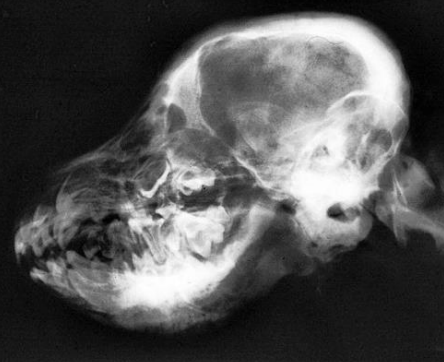

![]() | - mandible 쪽 경계가 무너져 있음. - skull 뒤쪽이 확연히 두꺼워져 있음. |